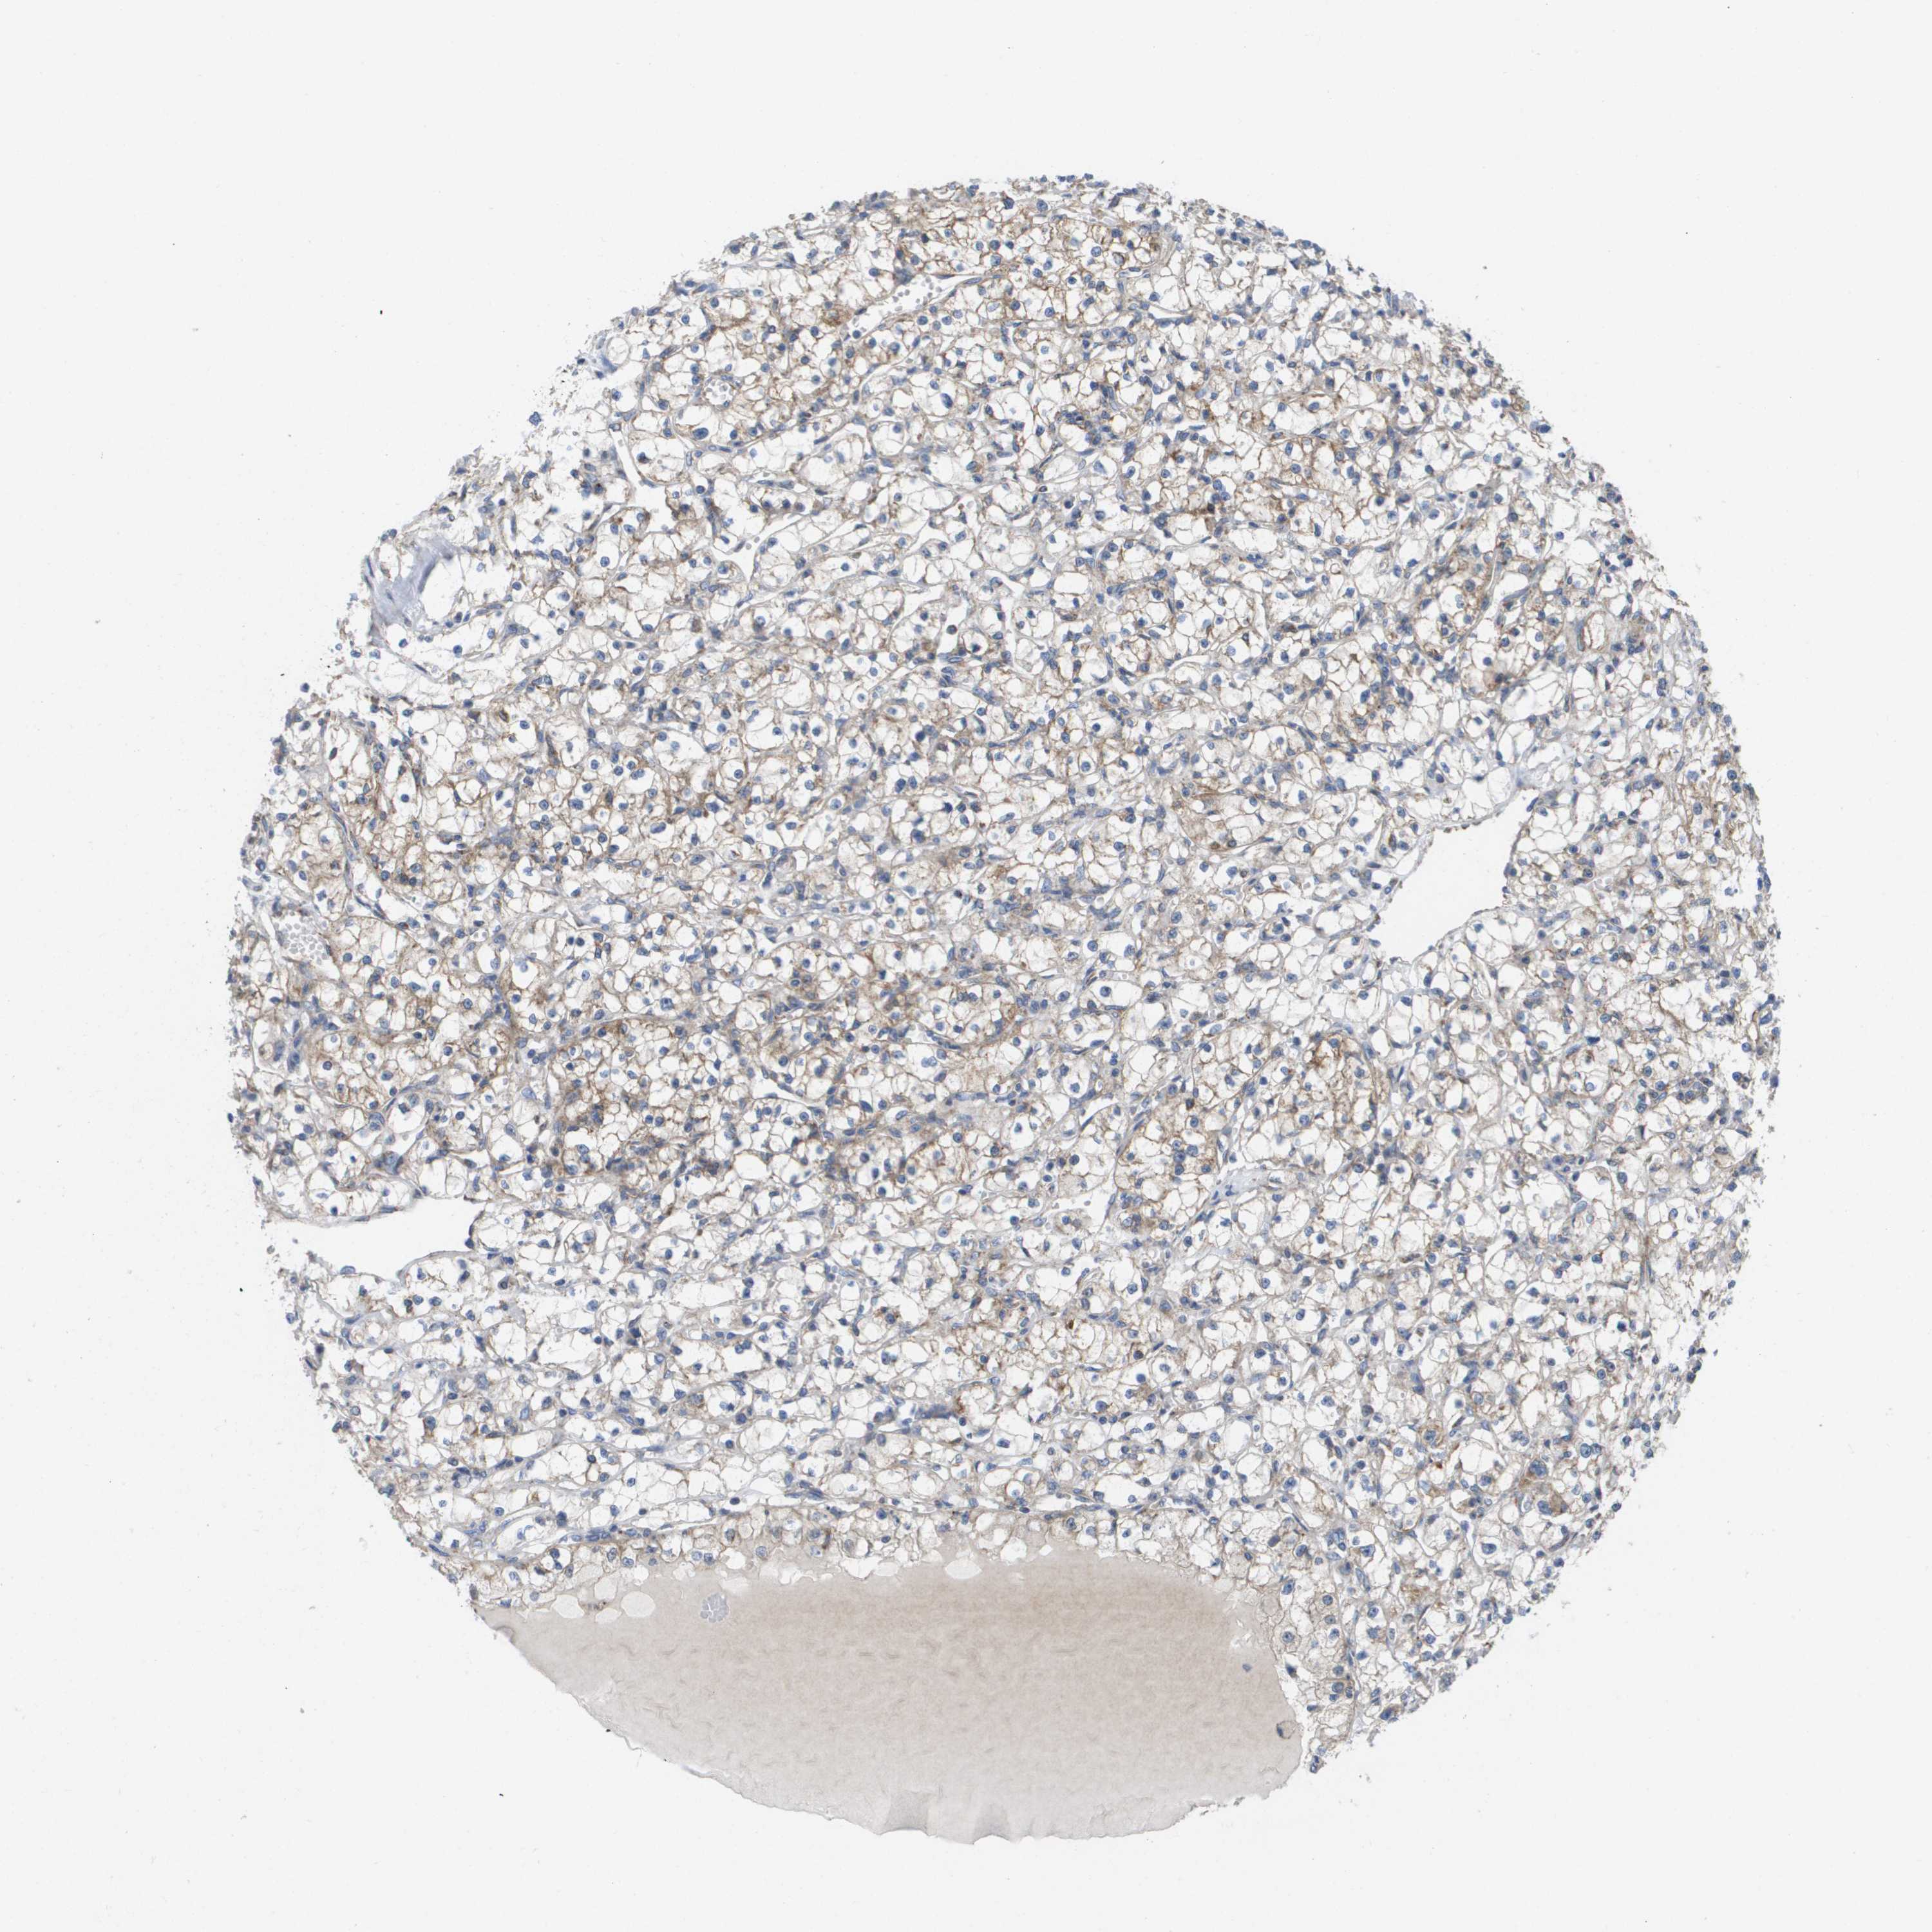

KIDNEY RENAL CLEAR CELL CARCINOMA (TCGA) - Interactive survival scatter ploti

The Survival Scatter plot shows the clinical status (i.e. dead or alive) for all individuals in the patient cohort, based on the same data that underlies the corresponding Kaplan-Meier plots. Patients that are alive at last time for follow-up are shown in blue and patients who have died during the study are shown in red.

The x-axis shows the expression levels (FPKM) of the investigated gene in the tumor tissue at the time of diagnosis. The y-axis shows the follow-up time after diagnosis (years). Both axes are complimented with kernel density curves demonstrating the data density over the axes. The top density plot shows the expression levels (FPKM) distribution among dead (red) and alive patients (blue). The right density plot shows the data density of the survived years of dead patients with high and low expression levels respectively, stratified using the cutoff indicated by the vertical dashed line through the Survival Scatter plot. This cutoff is automatically defined based on the FPKM cutoff that minimizes the p-score. The cutoff can be changed by dragging the vertical line or by entering a cutoff value in the square labeled "Current cut-off".

Under the Survival Scatter plot the p-score landscape (black curve; left axis) is shown together with dead median separation (red curve; right axis). Dead median separation is the difference in median mRNA expression between patients who have died with high and low expression, respectively. It is calculated as follows: median FPKM expression of dead patients with high expression - median FPKM expression of dead patients with low expression. This is intended to aid the user in visually exploring custom cutoffs and the associated p-scores and dead median separation.

Individual patient data is displayed and can be filtered by clicking on one or more of the category buttons on the top of the page. Categories describing expression level and patient information include: high, low, alive, dead, female, male and tumor stages. The scale of the x-axis can be toggled between linear and log-scale by clicking on the "x log" button. Mouse-over function shows TCGA ID, patient information and mRNA expression (FPKM) for each patient.

& Survival analysisi

Kaplan-Meier plots summarize results from analysis of correlation between mRNA expression level and patient survival. Patients were divided based on level of expression into one of the two groups "low" (under cut off) or "high" (over cut off). X-axis shows time for survival (years) and y-axis shows the probability of survival, where 1.0 corresponds to 100 percent.

FIS1 is potential prognostic, high expression is favorable in Kidney Renal Clear Cell Carcinoma (TCGA)

: 128.98

Average pTPM 148.2

Number of samples 521